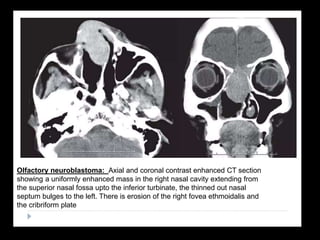

Esthesioneuroblastoma (ENB) • Alsoknown as Olfactory neuroblastomas,. • Rare malignant neuroectodermal tumor arising from olfactory mucosa. • Bimodal distribution - 2nd & 6th decade • Kadish Classification: A - nasal tumor, B - involvement of nasal cavity + sinuses, C - beyond sinuses, D – involvement of cervical lymph nodes.

• 54.

• CT: Cribriformplate destruction, bony remodelling of nasal cavity. •MRI: Intermediate-high signal on T2, dumb-bell shaped, avid enhancement, cysts in intracranial component -Peritumoural cysts between it and the overlying brain are often present, T2*GRE- blooming foci. • Treatment: Craniofacial resection + radiotherapy